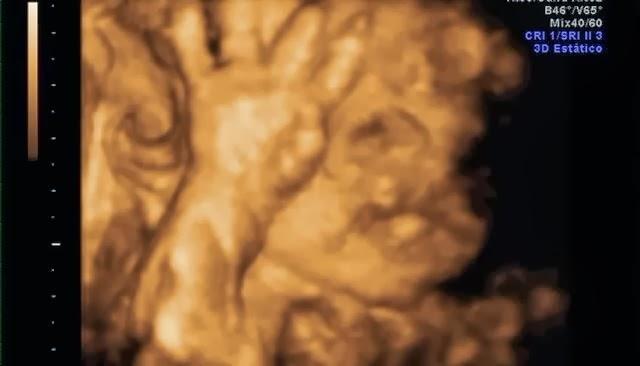

Su carita!Y estas son algunas capturas de pantalla de la eco 4d que me hice a principios de mes. Que ya de paso decir, que esta no me gustó NADA!! Tuvimos que esperar 2 horas para que nos cogieran, la eco nos la hicieron con prisas, y sólo se le vió la mitad de la cara.. así que para habernos gastado 100€ muy mal!! No os recomiendo la Ginecóloga de Gandia, Dra.Escrivá.

De momento parece que se parece a mami... jiji. Mi nariz, mi boca y mis mofletes :DEl padre se preguntó si era suyo.. jajaja, aunque tiene sus manazas.Y ahora os dejo unas fotitos de mi barriga en la playa, que aprovechando que esta semana aquí ha hecho muy buen tiempo nos hemos ido a hacernos un reportaje de fotos.